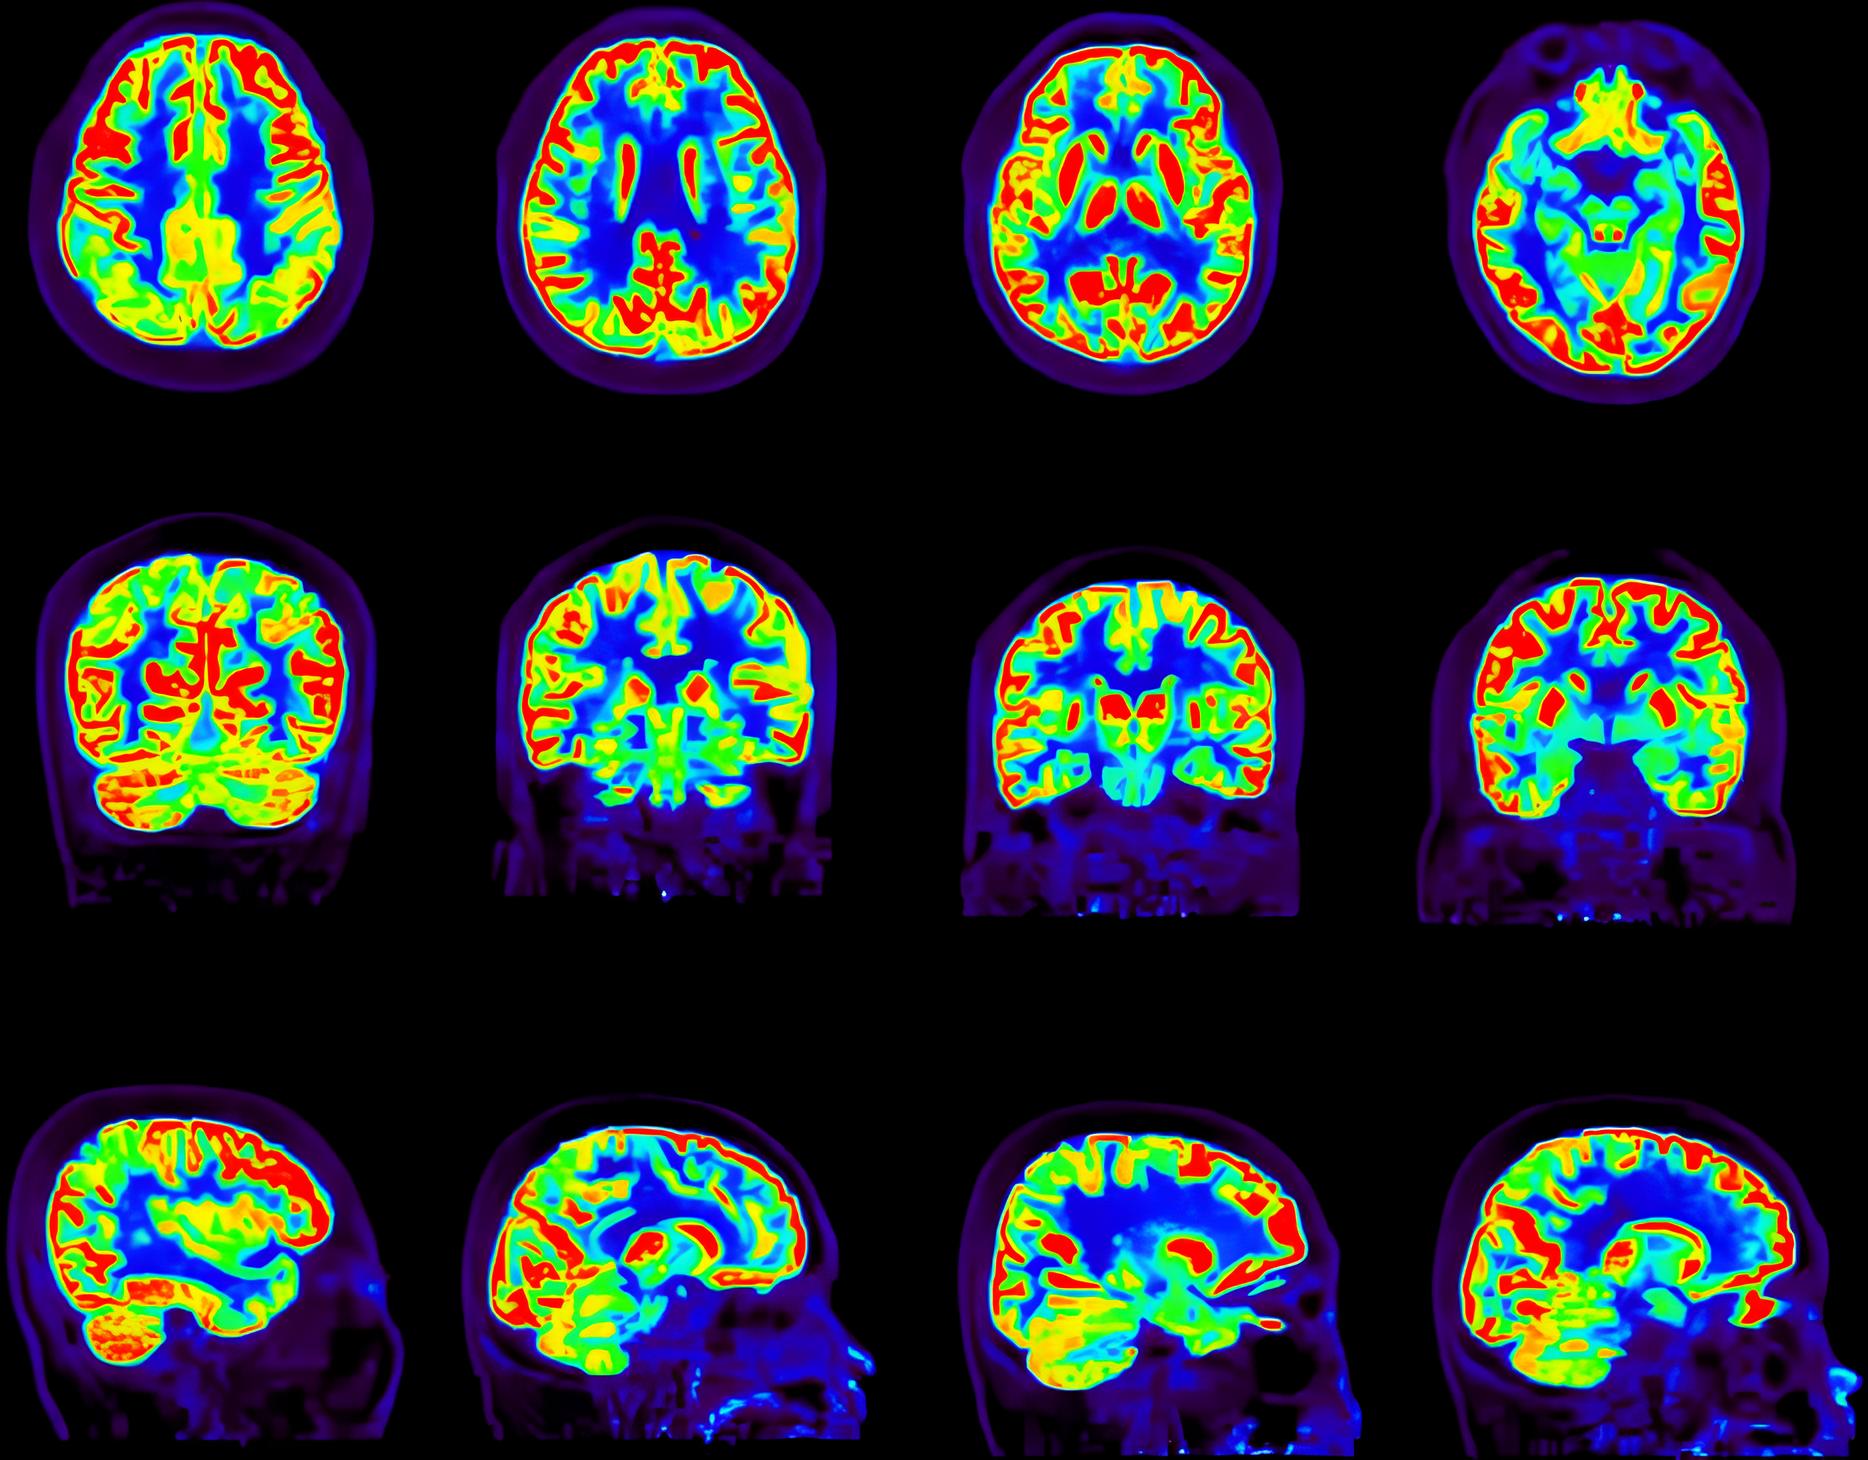

全采样重建

低计数图像重建

超低计数68Ga三符合重建

缺角度数据图像重建

采用单事件、低能量事件等全流程数据进行全数字PET图像重建,解决低剂量、多核素等场景下高质量成像问题。

传统算法 改进的算法 双符合重建68Ga和18F混合的信号 三符合重建仅含68Ga的信号 传统算法 改进的算法 缺角度系统